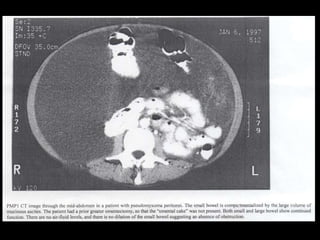

PMP : Diagnoses •CT : • Central displacement of the small bowel and compression of retroperitoneal structures • Peritoneal cavity full of PMP

Peritoneal cavity withmucinous tumor in the pelvis

Pseudomyxoma peritpnii Bowel wallthickening and fold swelling Multiple non-enhancing intraperitoneal masses